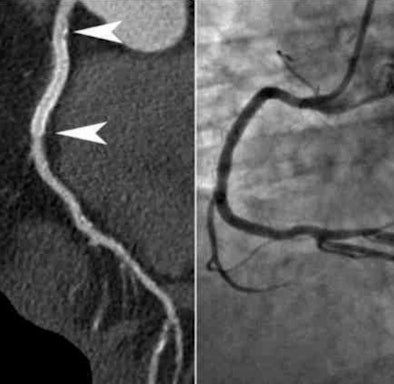

| Coronary CT angiography was performed in high-pitch flash mode after administration of atenolol and glyceryl trinitrate. The heart rate was 57 bpm, and the patient tolerated the procedure well at 100 kV with a total radiation dose of 0.85 mSv. Image courtesy of Dr. Ho Kheng Thye. |

Image quality was rated subjectively on a four-point scale depending on the degree of blurring -- with 1 being excellent and 4 nondiagnostic. The stents ranged in diameter from 2.75 to 4.0 mm.

Patients scanned at 80, 100, and 120 kV received doses of 0.38 ± 0.03 mSv, 0.90 ± 0.36 mSv, and 1.78 ± 0.15 mSv, respectively. One patient did not respond to beta-blockage (heart rate, 75 bpm) and was scanned in axial mode receiving a total dose of 2.46 mSv. The remaining 49 patients were scanned in flash mode.